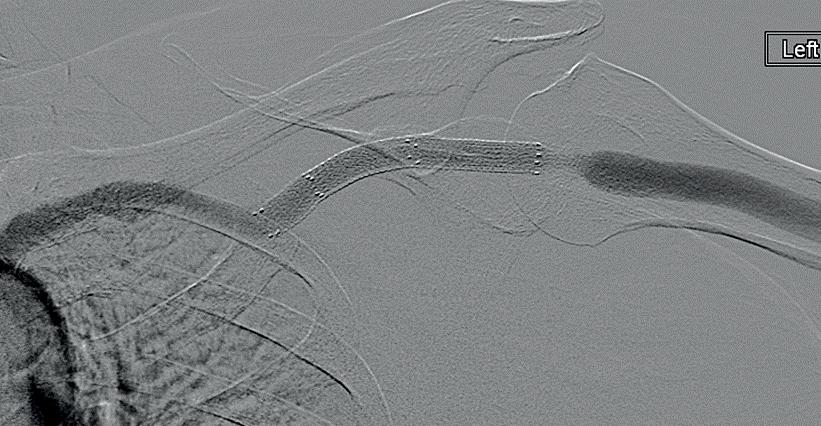

What would you do for this 57-year-old woman with a left brachiocephalic arteriovenous fistula?

Six weeks prior to this venogram, she had had recurrent cephalic arch stenoses treated with balloon angioplasty, and on the last intervention, the lesion lateral to stent graft had some recoil during balloon angioplasty. She is having dialysis for four hours, three

Image proved by Nicholas Inston with the patient's consent